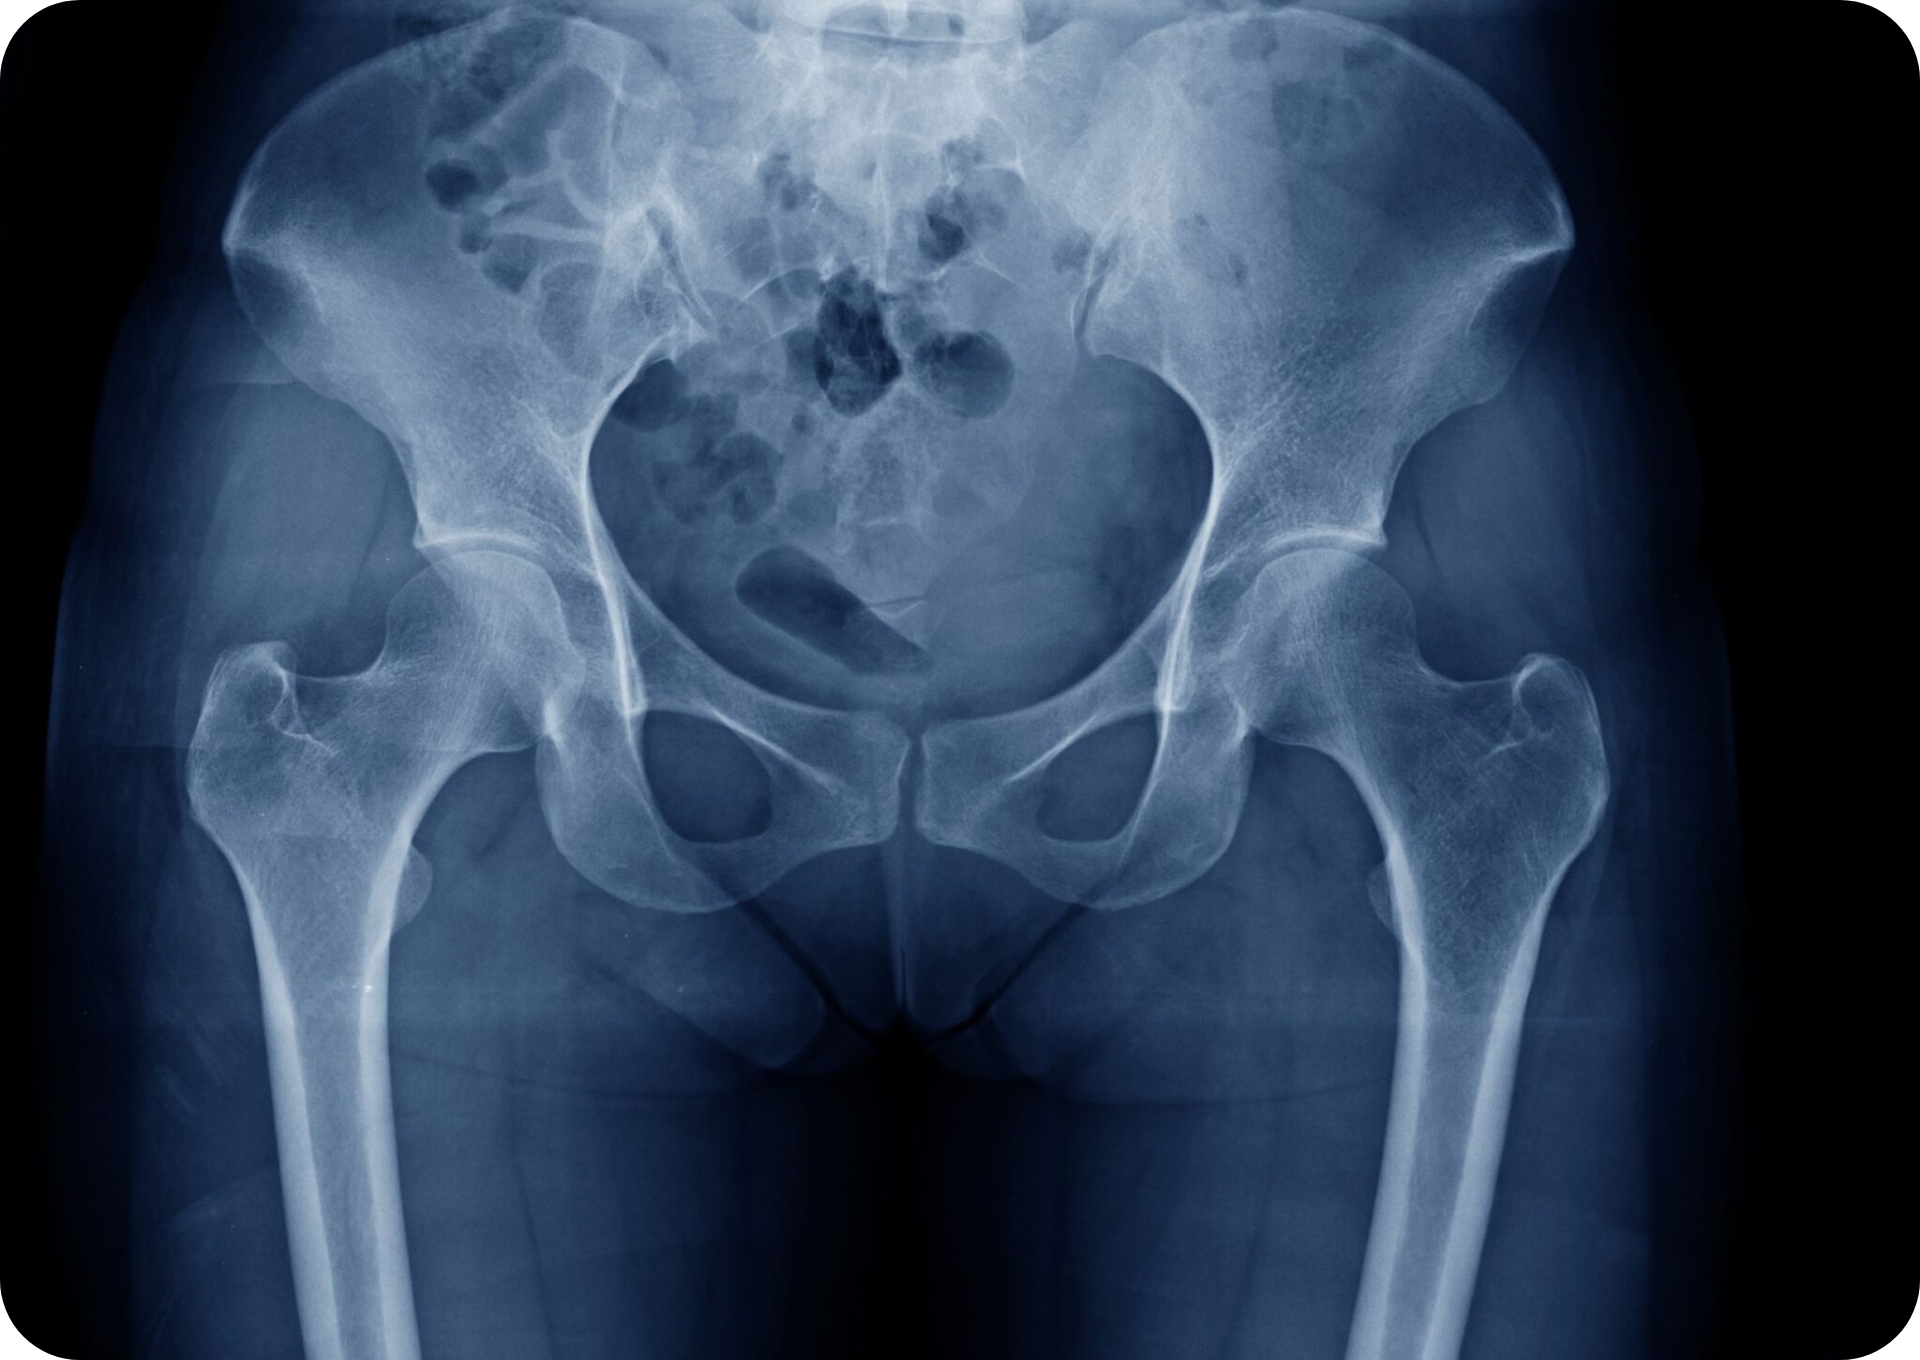

レントゲンでわかるの??

仙腸関節炎は、整形外科で行われる様な一般的なレントゲンやMRI、CT検査において異常がみられないため、診断が難しく見逃されることが多々あります。